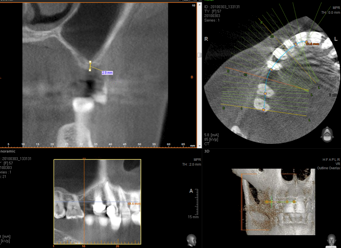

L’implant doit être entouré d’un os suffisant en qualité et en quantité.

Le problème le plus fréquent est un manque d’os, là où l’on souhaite poser un implant.